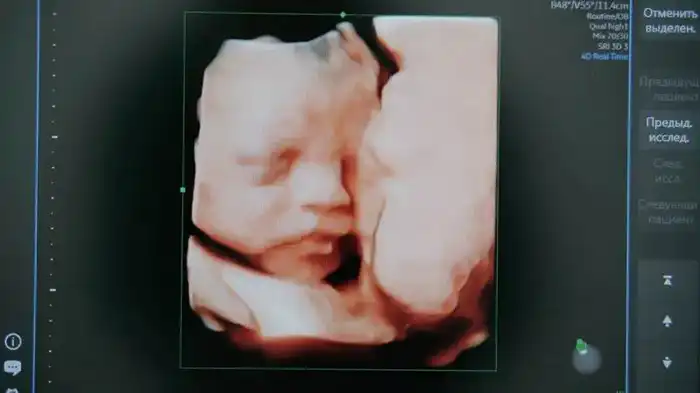

Проект основан на системе искусственного интеллекта, разработанной на платформе Yandex Cloud. Она предназначена для анализа изображений, полученных при первом скрининге, который проводят на 11—14 неделе беременности. Заместитель акима Карагандинской области Ораз Таурбеков отметил, что это важный шаг к улучшению диагностики.

Система будет анализировать результаты УЗИ беременных, обрабатывая только изображения без использования персональных данных. Облачные технологии Yandex Cloud помогут в хранении и обработке данных, обеспечивая высокую точность диагностики.